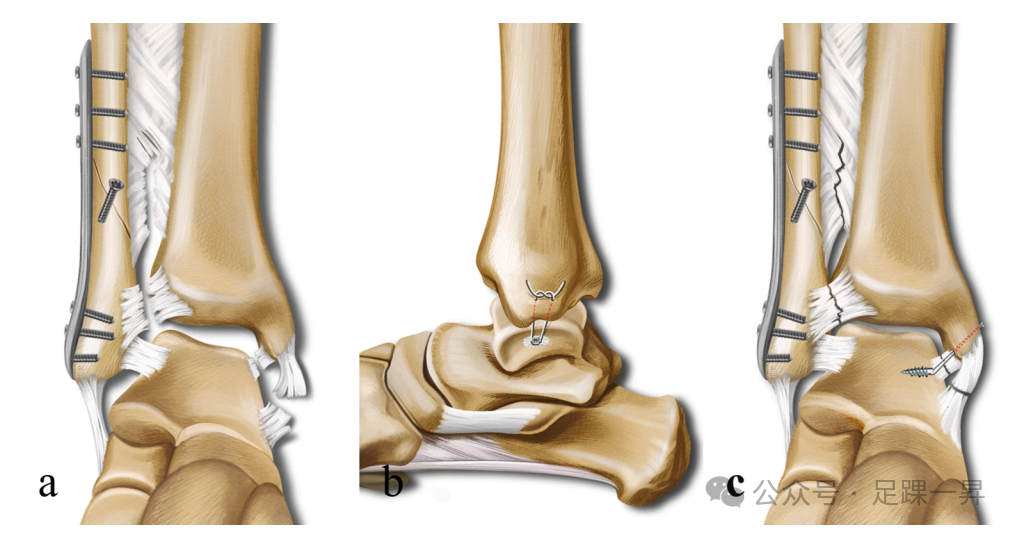

手术均在止血带下仰卧位进行。首先,通过外侧入路,按照标准AO原则,暴露腓骨骨折并进行解剖复位,采用合适长度的锁定钢板固定。随后进行外旋应力试验和拉钩试验,证实三角韧带和下胫腓联合不稳定。若应力试验显示踝关节内侧间隙≥5mm且下胫腓间隙增宽>2mm,则将患者纳入研究。

在内踝中央做一弧形切口,通常可看到破裂的三角韧带浅层,偶见其嵌入内踝骨折间隙。随后,将胫后肌腱向后牵开,踝关节外翻,暴露三角韧带深层。在距骨体内侧三角韧带深层止点中心,平行于距骨穹窿植入1枚2.5mm导针,随后植入5.0mm缝合锚钉。接着,使用1.5mm克氏针,沿三角韧带止点方向,在内踝钻2个斜孔(1个位于丘间沟水平,1个位于后丘)。将与锚钉相连的4根缝线通过这2个孔引出,每个孔2根缝线。最后,将踝关节置于矢状面90°、内翻位,将缝线固定于踝关节内侧胫骨皮质。重复外旋应力试验,检查踝穴完整性及稳定性,最后直接缝合三角韧带浅层。